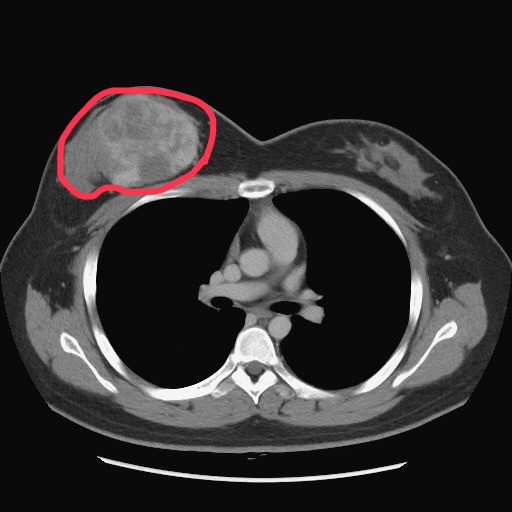

▲電腦斷層影像可見陳小姐右乳房的葉狀瘤(紅圈處)。(圖╱臺中榮總提供)

台中25歲陳小姐去年初摸到右側乳房有硬塊,以為是生理週期的正常腫脹,未料2週內腫塊快速成長至胸部大了近一個罩杯。臺中榮總乳房外科洪志強主任安排切片檢查確診為乳房葉狀瘤,因腫瘤已約9公分大且考量腫瘤周邊安全距離,右乳房須全切除。陳小姐說,當下腦筋空白,引以為傲的乳房須切除,切除後又意外發現懷孕,一想到孩子可能問「媽媽你的胸部為什麼跟別人不一樣!」讓她更確定重建決心。在整形外科呂俊德主任、婦女醫學部林俐伶醫師合作下,於懷孕8週時接受8小時的自體腹部皮瓣重建乳房手術,並順利於去年11月迎接兒子出生,開心投入育兒生活。

臺中榮總乳房外科洪志強主任表示,乳房葉狀瘤由乳房間質組織增生形成,與一般乳房惡性腫瘤是由乳腺管增生不同。發生原因不明確,但醫學普遍認為可能和荷爾蒙及基因突變有關,其生長速度快、少有疼痛感,因此病人大多經自我觸診發現,也可能因腫瘤牽扯表皮致外觀變形而發現。乳房葉狀瘤發生率低,西方統計數據顯示,約占女性乳房腫瘤0.3-1%,好發於40-50歲女性,然任何年齡的女性都可能罹患葉狀瘤。葉狀瘤經切片組織型態病理分類為良性(占所有葉狀瘤50%以上)、邊緣性(borderline)及惡性。標準治療方法是手術切除,不需要像一般乳癌般接受淋巴結切除、化學治療或放射線治療。陳小姐診斷為邊緣性葉狀瘤,因腫瘤大且為確保周邊組織安全距離,降低復發及轉移機率,因此建議切除整個右乳房。